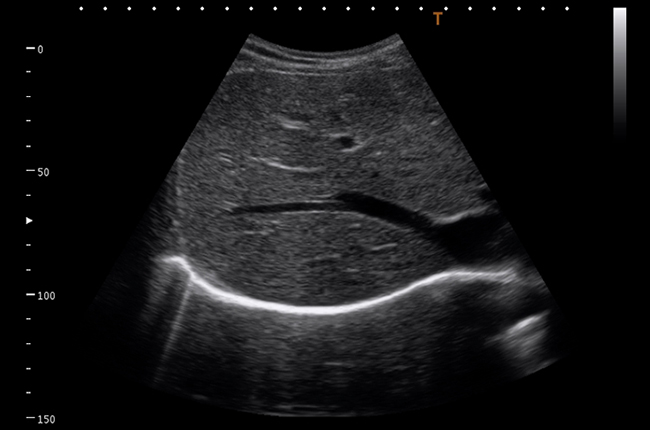

Якщо Вам потрібна висока якість діагностики завжди і всюди, Viamo c100 — це ідеальне рішення. Система Viamo c100 поєднує в собі всі переваги переносної ультразвукової системи та діагностичну точність, ефективність і зручність, які притаманні стаціонарним апаратам.

Viamo c100 – сканер, розроблений для ситуацій, де мобільність – необхідний чинник, а якість зображення має вирішальне значення. Апарат належить до експертного класу та підтримує технології візуалізації останнього покоління, що дозволяє отримати зображення неперевершеної якості – основний чинник успішної діагностики в ургентних ситуаціях.

Підтримка широкої лінійки широкополосних мультифокальних датчиків з частотою до 14 MHz.